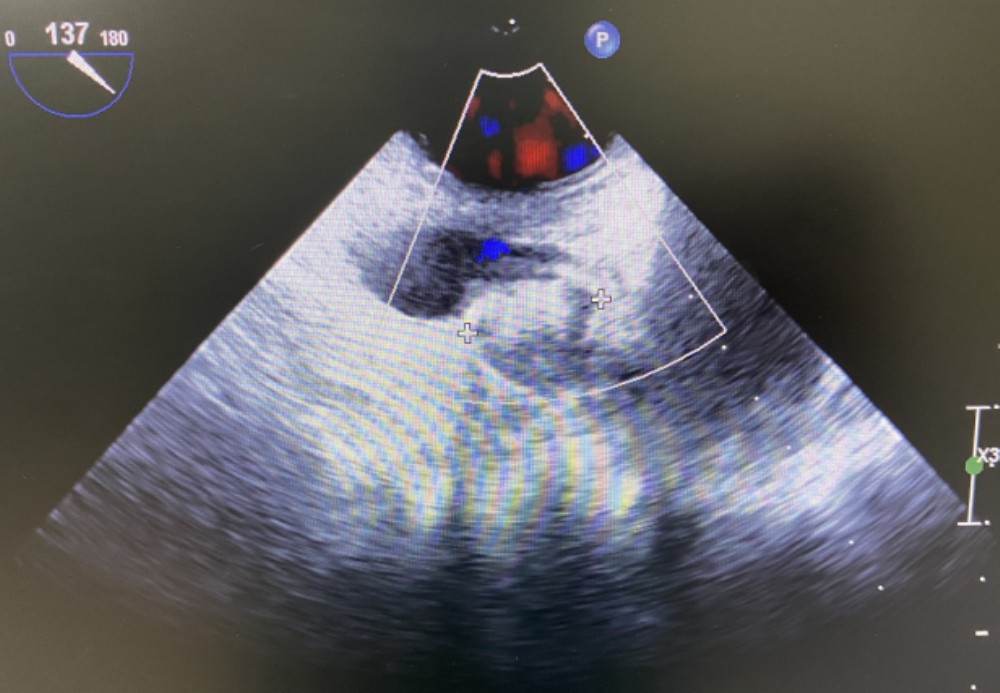

术中TEE影像图

经过充分的病情沟通后,手术团队成功为患者实施冷冻球囊消融联合左心耳封堵术的“一站式”治疗,为患者成功解决困扰多年的房颤问题和因房颤可能导致的其他并发症。